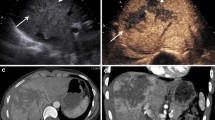

Gross pathology, CEUS, and CECT images of grade III renal trauma with active bleeding at baseline are shown in Fig. 3a–c and in mild shock are depicted in Fig. 3d–f. Figure 3g–i shows images of grade III renal trauma with active bleeding in moderate shock and Fig. 3j–l is images for grade IV renal trauma with active bleeding in severe shock.

(a–c) Gross pathology, CEUS, and CECT images of grade III renal trauma with active bleeding (yellow arrow) at baseline; (d–f) gross pathology, CEUS, and CECT images of grade III renal trauma with active bleeding (yellow arrow) in mild shock; (g–i) gross pathology, CEUS, and CECT images of grade III renal trauma with active bleeding (yellow arrow) in moderate shock; (j–k) gross pathology, CEUS, and CECT images of grade III renal trauma with active bleeding (yellow arrow) in severe shock. CEUS contrast-enhanced ultrasonography, CECT contrast-enhanced computed tomography

Before shock, the kidneys were brightly colored, with an intensive cortical vascular distribution and a steady pulse (Fig. 3a). Overall, 76 % (19/25) of the dogs showed renal trauma on conventional US, but accurate classification was not possible. In contrast, CEUS showed constriction of the renal arteries within the trauma region at all stages of shock, with the region of trauma being either not enhanced or only weakly enhanced. Trauma diagnosis by CEUS was 80 % accurate for grade III (8/10) and 100 % accurate for grade IV (15/15) traumatic incisions. During active bleeding, visible contrast agent flowing out from the rupture in the renal capsule was considered to indicate either no or low contrast enhancement (Fig. 3c).

Gross examination showed no bleeding in any of the 25 wounds during the stage of severe shock (Fig. 3j). CEUS showed that with progressive shock, the flow of the contrast agent slowed significantly, and arteries at all depths became more constricted. The contrast agent slowly filled the renal capsule, accumulated in the vascular endings, and dispersed, resulting in reduced intensity of contrast enhancement and extended WT. During the stage of severe shock, perfusion of the renal parenchyma declined, and the intensity of contrast enhancement decreased. The diagnostic sensitivity of CEUS declined to 60 % for grade III (6/10) and 80 % for grade IV trauma (12/15) (Fig. 3e, h, k).

Comparison of CEUS and CECT results

On CECT examination, the renal lesion appeared as a low attenuation area when the kidney capsule was incomplete, and active bleeding appeared as high attenuation areas (Fig. 3c). During the baseline and mild shock stage, sonograms obtained after the intravenous injection of contrast agent showed marked contrast medium extravasation and pooling at the site of active bleeding (Fig. 3b, e). Graded hypotension resulted in a significant, stepwise diminution in renal blood flow on both CEUS and CECT. As shown in Table 2, no significant difference was found in the shock detection rate between CEUS and CECT during any stage of shock (P > 0.05). CECT imaging showed kidney shrinkage, with a decrease in both the areas of enhancement and irregular non-enhanced areas (Fig. 3f, i, l).